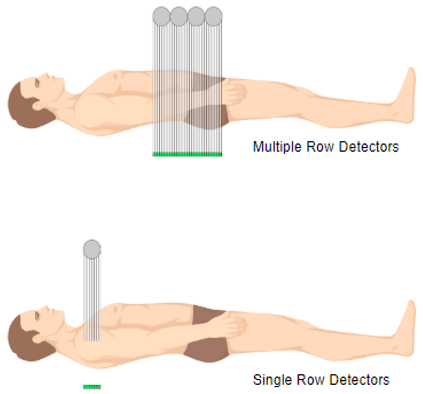

Multi-Detector Configuration

One major problem with a single slice, a single row detector is related to the length of time needed to acquire the data. Multidetector configuration is a form of computed tomography (CT) technology for diagnostic imaging. In MDCT, a two-dimensional array of detector elements replaces the linear array of detector elements used in typical conventional and helical CT scanners. The two-dimensional detector array permits CT scanners to acquire multiple slices or sections simultaneously and greatly increase the speed of CT image acquisition.